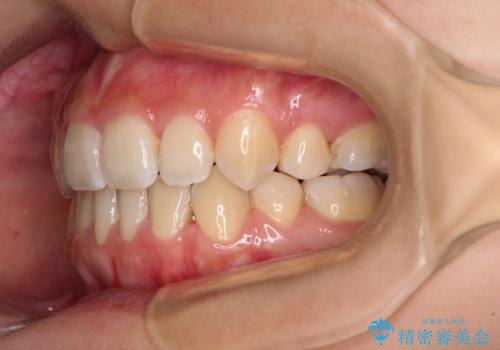

デコボコと八重歯の目立つ前歯 ワイヤー装置による抜歯矯正

- 上下前歯のデコボコと八重歯を気にして来院された患者様です。

叢生を解消する際に出っ歯とならないようにするために、上下左右の小臼歯計4本を抜歯することとしました。

奥歯の咬み合わせが理想的であり、歯の移動に時間のかかる出っ歯でもなかったため、2年程度で治療を終えることを目標としましたが、無事に予定通りの2年間で終えることができました。